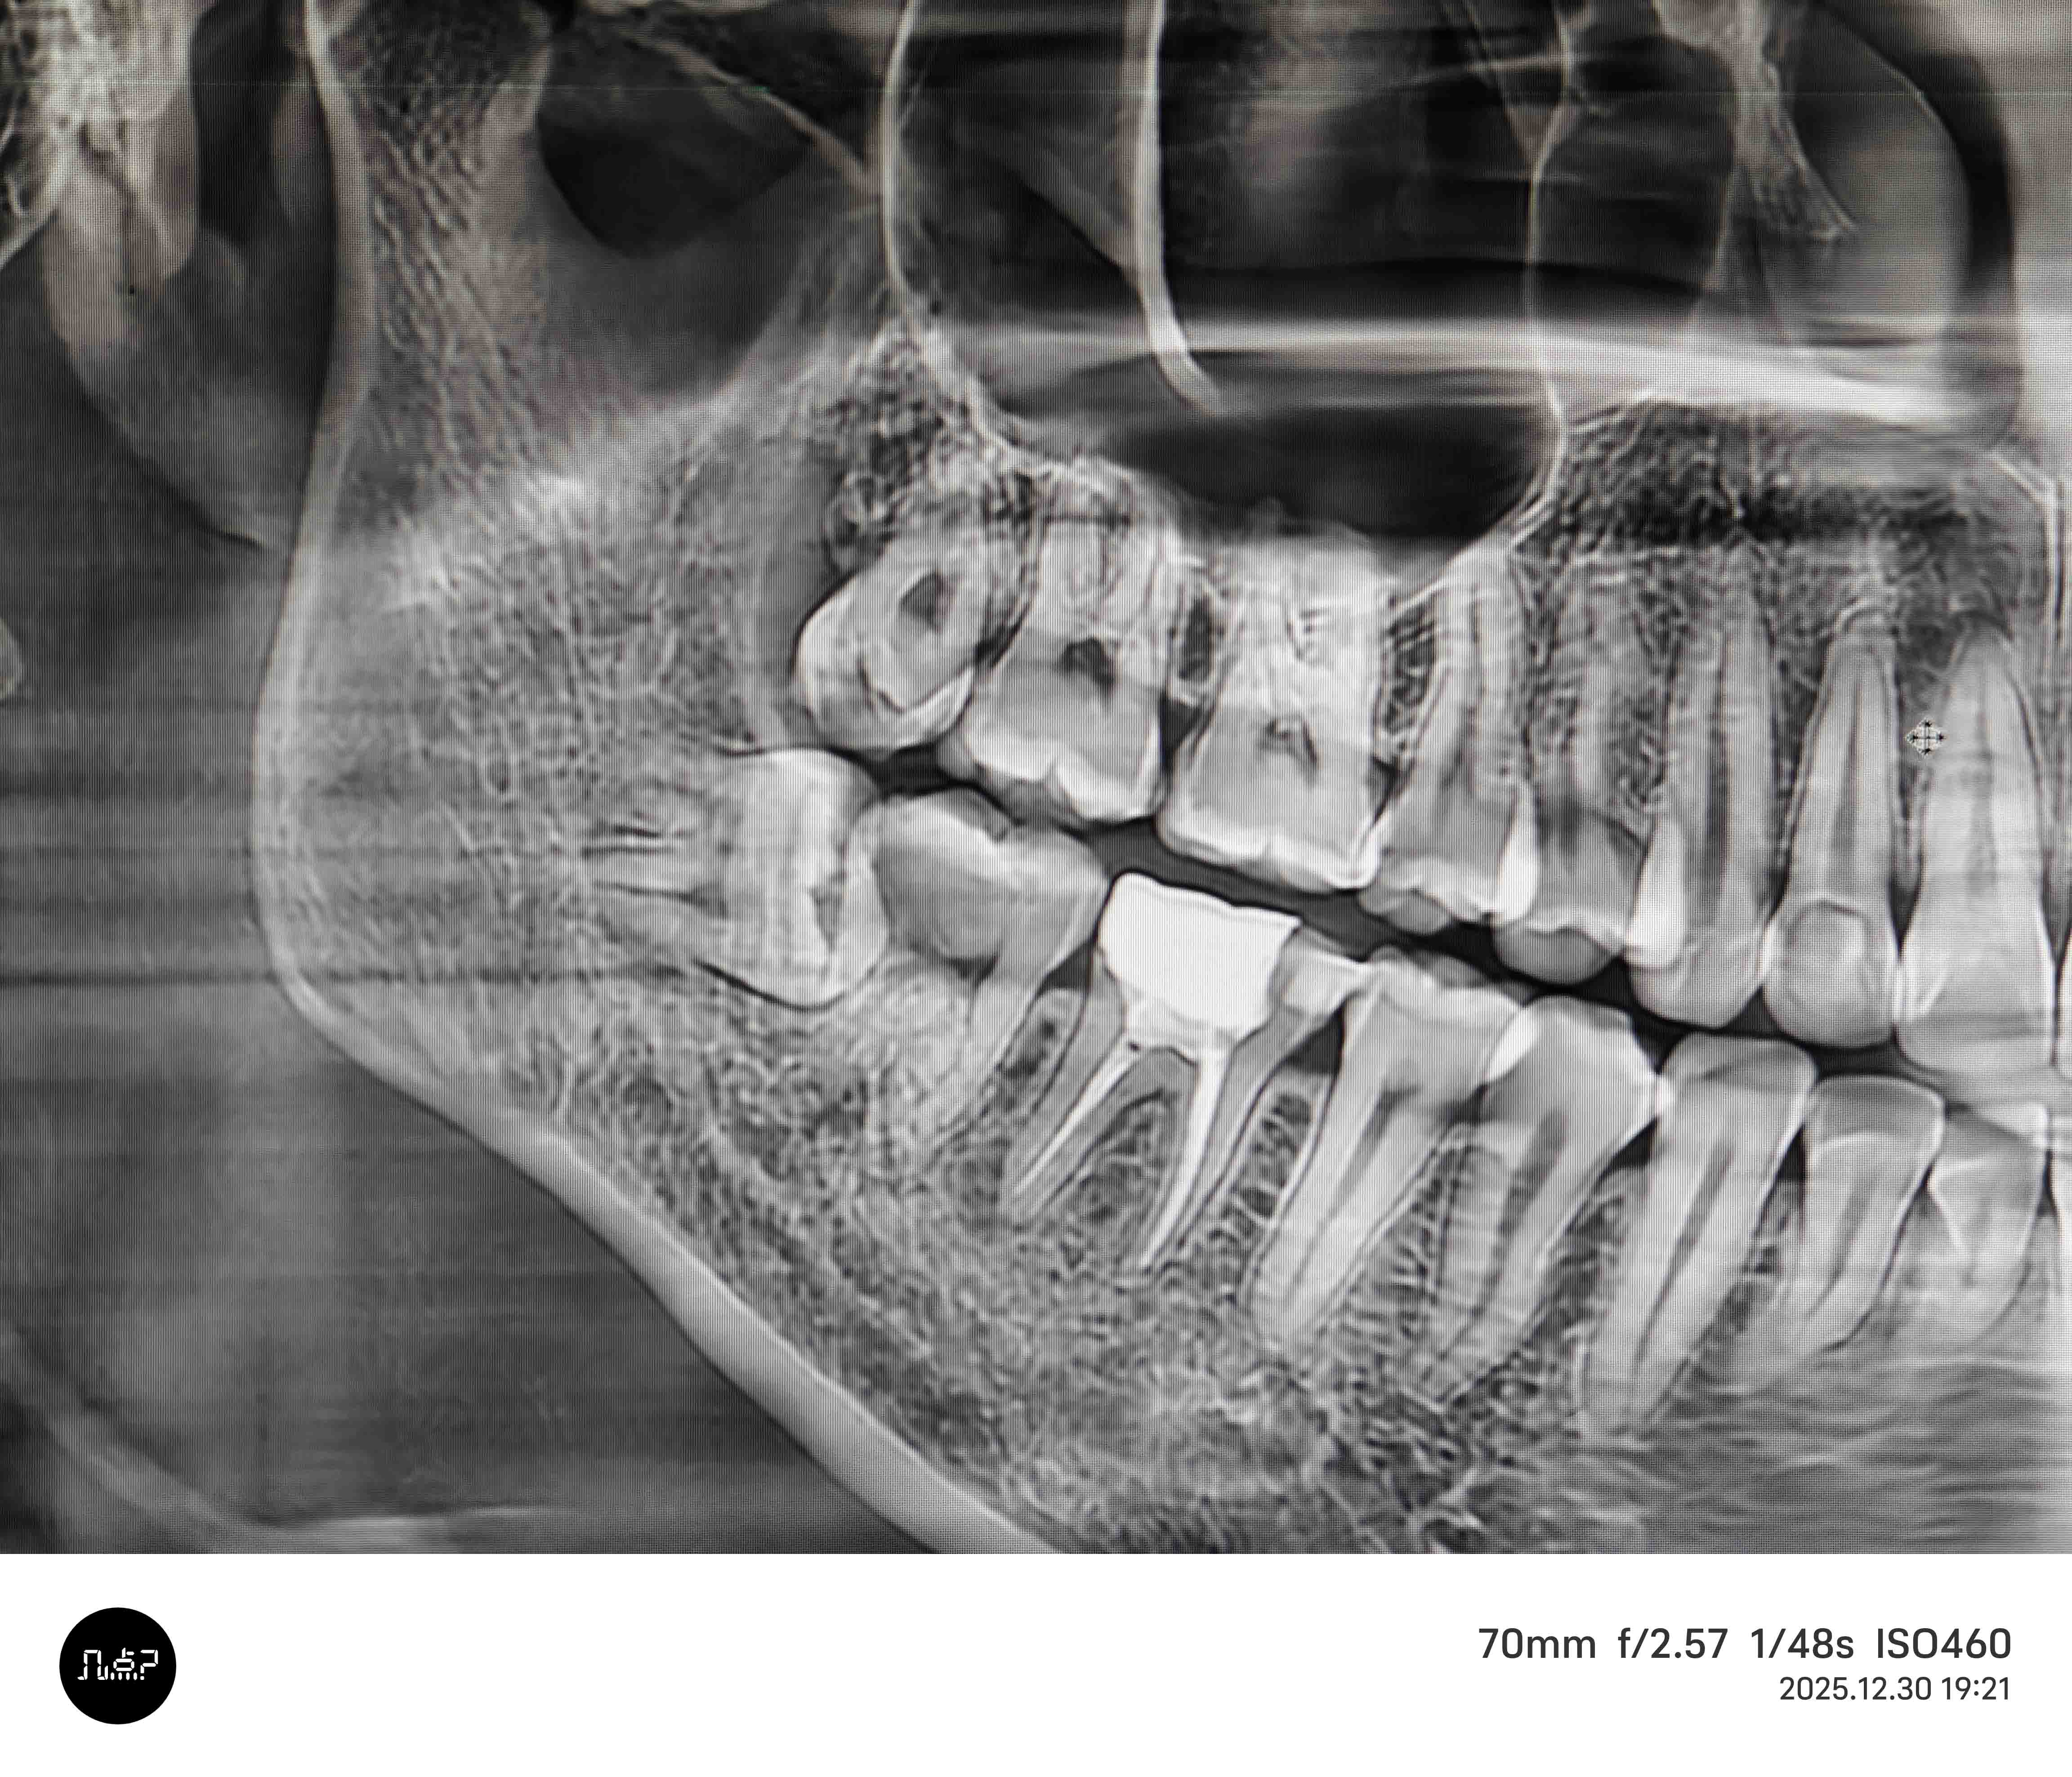

根管治疗

根管治疗 - 案例一

术前 术前

术后 术后

根管治疗 - 案例二